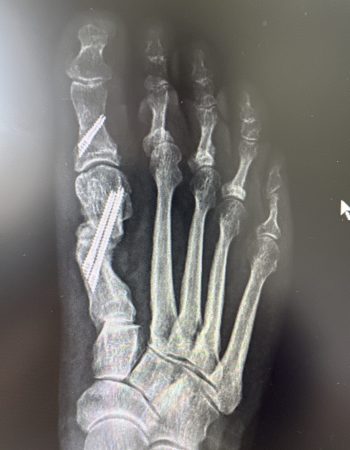

Os presento un caso de deformidad de hallux valgus intervenido con una técnica de cirugía percutánea de 3ª generación. En este ocasión, se ha realizado unas osteotomías en el primer metatarsiano y en la primera falange que se han fijado con tornillos que confiere a la corrección estabilidad, seguridad y menor dolor postoperatorio manteniendo el respeto a las partes blandas.

Los resultados radiográficos y clínicos los podéis ver en las fotos antes de la cirugía y los 3 meses de la misma.